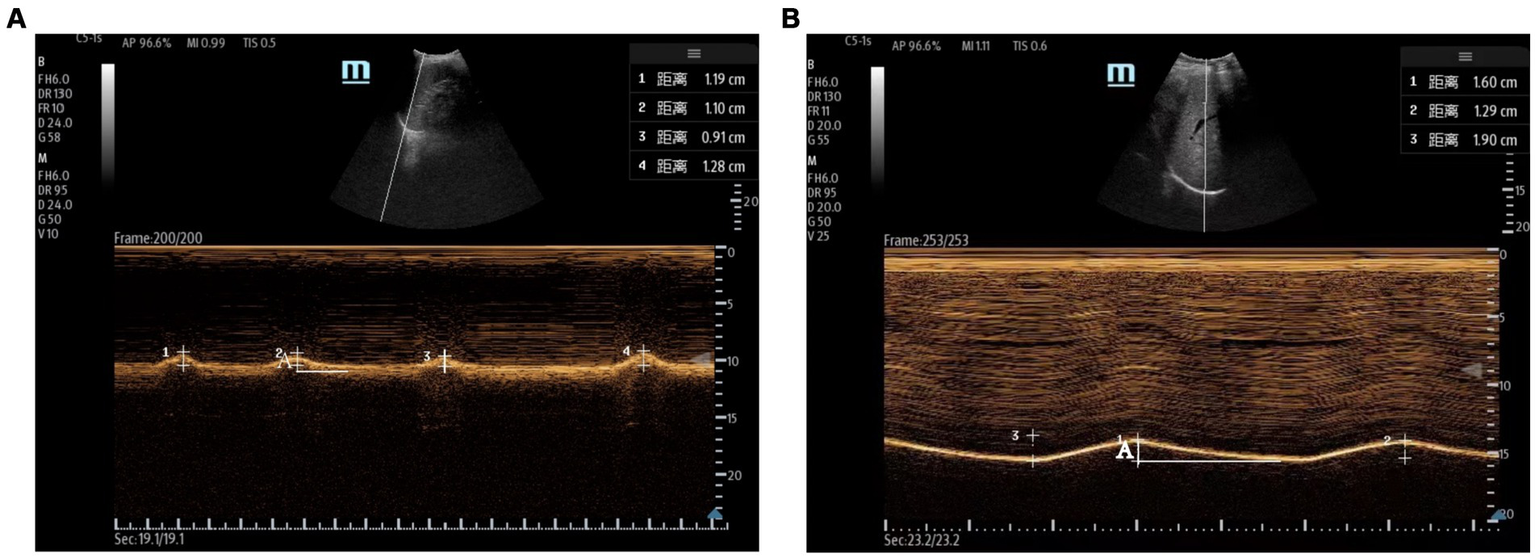

Measurements of DT and DTF require the use of a high-frequency linear ultrasound transducer (3–12 MHz). The patient should be in a semi-recumbent position, and the probe should be placed in the midaxillary line at ribs 8–10, perpendicular to the intercostal space. In B-Mode, the diaphragm can be visualized as a three-layered structure, with the upper hyperechoic layer being the pleura, the lower layer being the peritoneum, and the middle layer being the diaphragm (29) (Figures 2A,B). In contrast, DE measurements are performed using a low-frequency abdominal convex probe (3–5 MHz), the patient should be positioned at a 45-degree semi-recumbent angle, and the ultrasound probe should be placed parallel to the right costal margin at the right midclavicular line, using the transverse section of the liver as an acoustic window. Alternatively, the probe can be placed perpendicular to the costal margin to obtain a longitudinal section of the liver (Figures 2C,D). It is also possible to obtain diaphragm images at different interfaces using liver vessels as markers, however, this method is not commonly used (Figure 3). In B-Mode, the high echo shadow covering the liver surface represents the diaphragm, switching to M-Mode allows for the observation of the diaphragm waveform synchronized with the respiratory cycle (Figure 4B). On the left side, the probe is placed at the 8–10th rib along the midaxillary line, parallel to the intercostal spaces, the other methods are the same as for the right side (Figure 4A) (29). Ultimately, ultrasound is clinically reproducible (32) and has become an essential tool for most clinicians, its overall measurement failure rate has decreased from 27% a decade ago to 0.7% today, demonstrating the effectiveness of ultrasound technology (33).

Figure 4

Evaluation of the diaphragm using ultrasound. (A) Left measurement of diaphragmatic excursion measured with the spleen as the acoustic window. (B) Right diaphragmatic excursion measured using the liver as an acoustic window. The total length of A is the diaphragmatic excursion for one respiratory cycle.